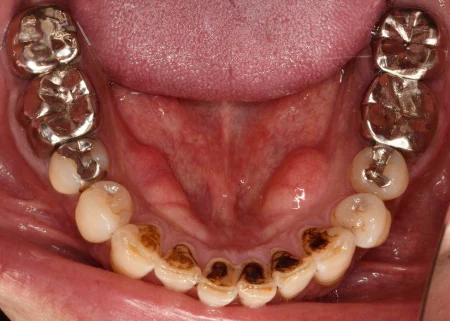

治療前

| カウンセリング・診断結果 | 拝見したところ、左右下の前歯6本(中切歯/1番、側切歯/2番、犬歯/3番)の裏側は、重度の着色により黒くなっていました。 また、歯と歯茎の境目や歯と歯の間には固い汚れ「歯石」の付着も見られました。 患者様に伺ったところ、「1日約15本ほど喫煙する」とおっしゃっていました。 着色や歯石があることで歯の表面がざらつき、汚れ「プラーク(歯垢)」の付着を招きやすくなります。 それによって歯周病や虫歯のリスクがあるため、着色や歯石の除去が必要と診断しました。 |